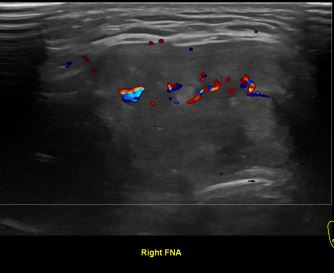

상기환자 외부건진 이상소견으로 조직검사위해 내원하신 40대 초반 여성분으로

의심스러운 갑상선 우엽 세포검사후 갑상선암으로 진단되었습니다